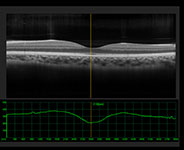

Slit Lamp Examination

A close-up evaluation of the eye’s lens and structures.